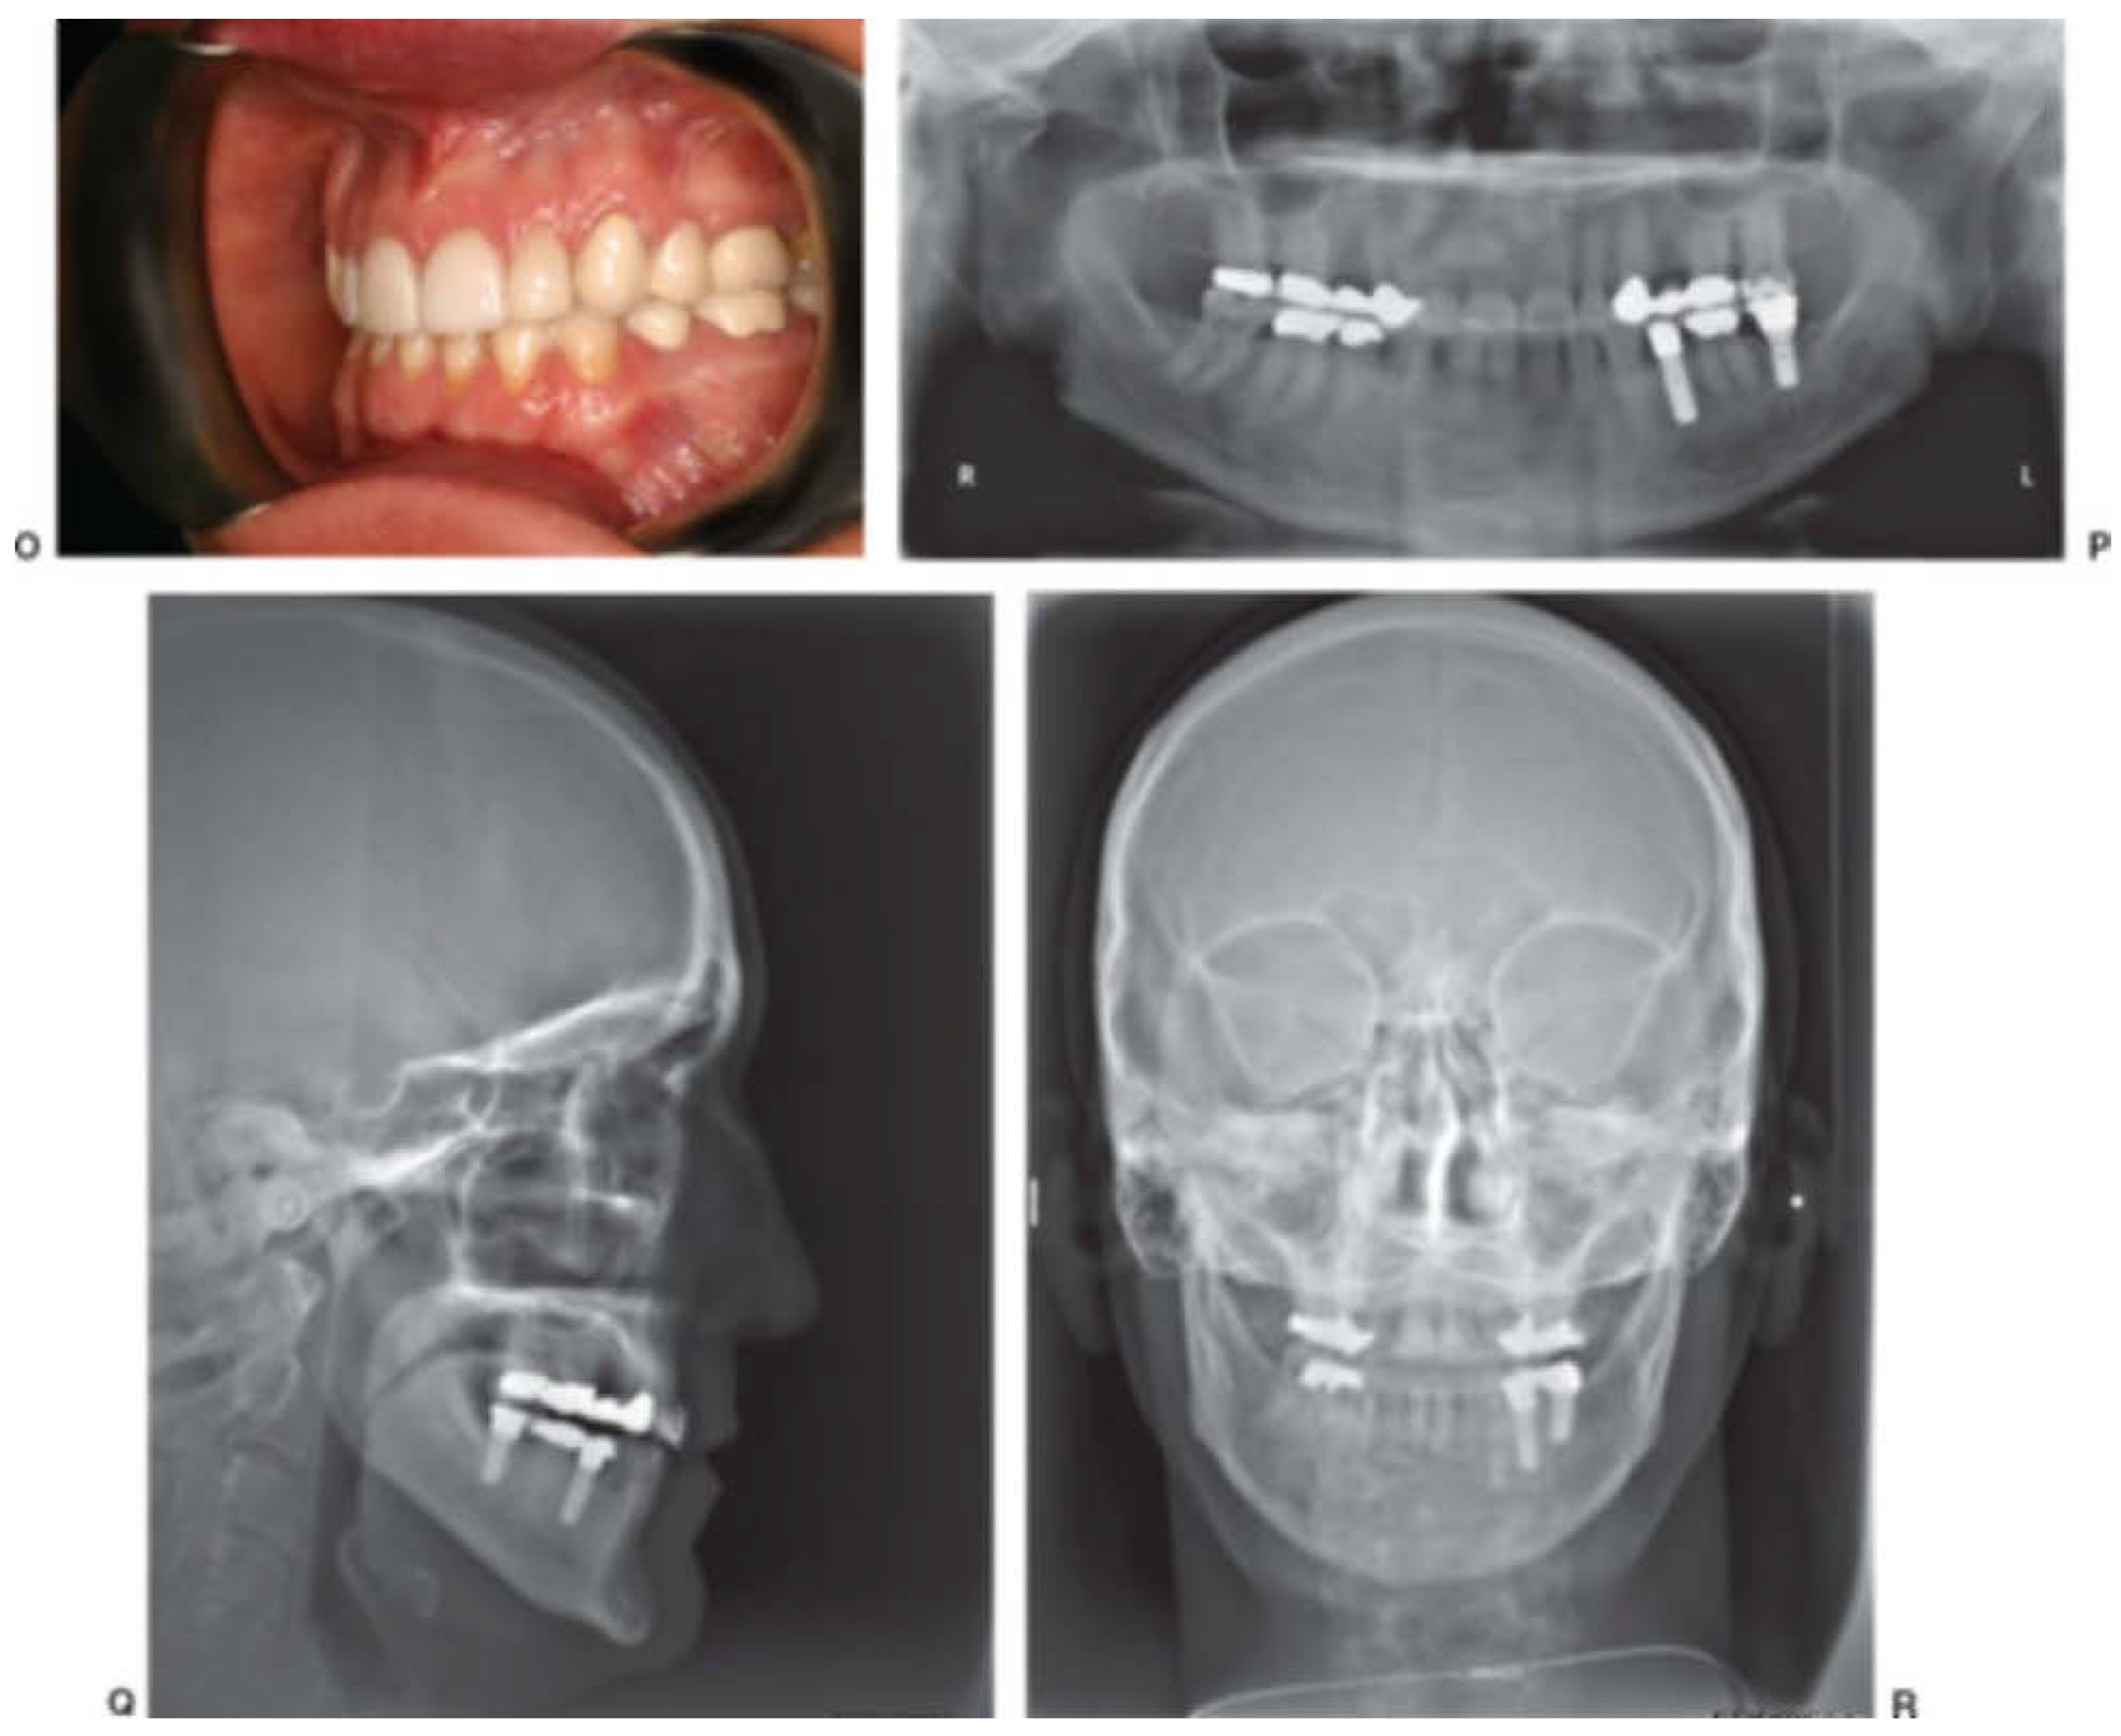

Figure 5. Patient with right unilateral condylar fracture that went untreated for 11 weeks. Frontal (A) and open-mouth (B) photographs demonstrated slight deviation of the mandible to the right and good mobility of mandible. Her occlusion (C–E) showed premature contact on the right posterior, deviation of the mandible to the right, and slight open bite on the left. The panoramic radiograph showed a high condyle fracture on the right (F). She was taken to surgery and when under a general anesthetic, her mandible deviated to the right (G). However, it was easy to reposition it into a normal occlusion (H). Arch bars were applied, and she was treated as a fresh condyle fracture patient, with a class II elastic on the right side (I), allowing her to close into a proper occlusal relationship (J). She was weaned from the elastic over a 6-week course, at which time her occlusion was normal. Frontal (K) and open-mouth (L) photographs taken 3 years later show she has good facial symmetry but some deviation to the right on opening. Her occlusion (M–O) remained stable. A panoramic radiograph shows the malunion of the condylar fragment, which now articulates with the articular eminence (P). A lateral cephalogram shows a normal maxillomandibular relationship (Q). A P-A cephalogram (R) shows no facial asymmetry.